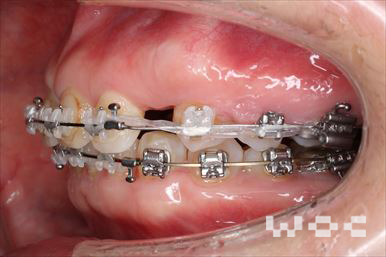

上下舌側矯正を希望。上顎両側第一小臼歯の抜歯としたが上顎右側第二小臼歯は治療した歯であったため、抜歯部位を変更。治療の難度が上がったため治療期間が少し延長しました。

- 年齢:33歳女性

- 主訴:出っ歯、前歯で噛めない

- 基本矯正料金:1,295,000円

- 治療期間:2年8ヶ月

- 抜歯部位:上顎右側第二小臼歯、左側第一小臼歯